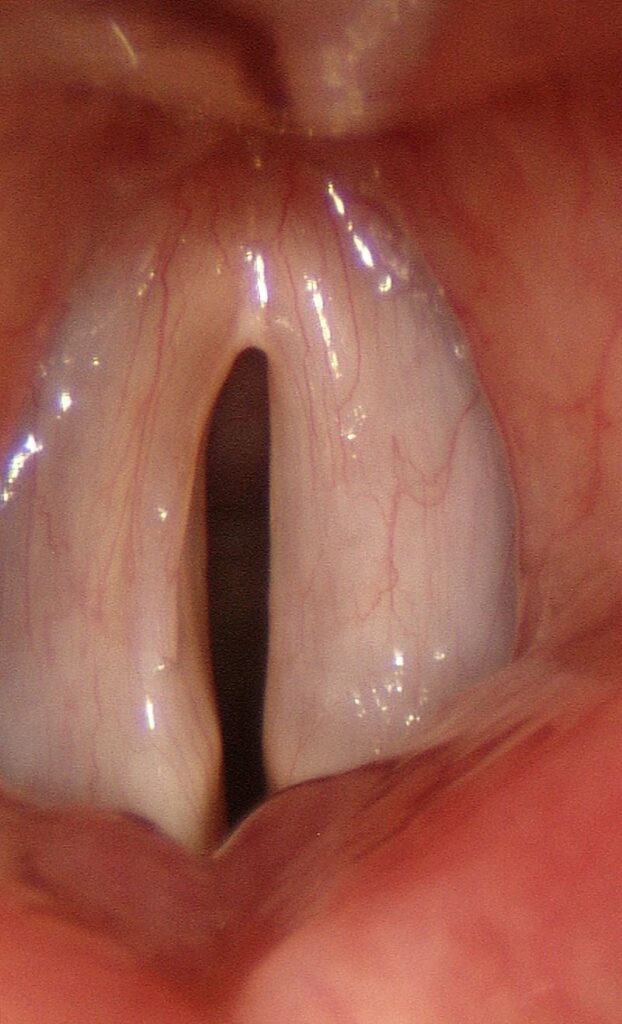

Split Gap

Vocal overdoers typically develop a callus or swelling in the very center of the membranous vocal cord. This protuberant swelling will touch first as the vocal cords are tensed, leaving an opening both anterior and posterior to it — a split gap. It is best visualized at higher pitches. As the vocal cords tighten, any marginal swelling is pushed further medially and made more visible to the examiner.